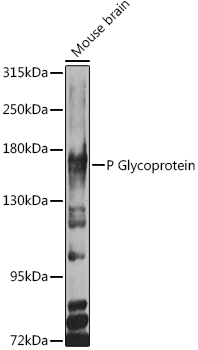

ApplicationsImmunoFluorescence, ELISA, ImmunoHistoChemistry

- ApplicationsImmunoFluorescence, ELISA, ImmunoHistoChemistry

- Target descriptionATP binding cassette subfamily B member 1

- Target synonymsABC20; ATP-binding cassette, sub-family B (MDR/TAP), member 1; ATP-dependent translocase ABCB1; CD243; CLCS; colchicin sensitivity; doxorubicin resistance; GP170; MDR1; multidrug resistance protein 1; p-170; P-glycoprotein 1; P-GP; PGY1; phospholipid transporter ABCB1

- Protein NameMultidrug resistance protein 1